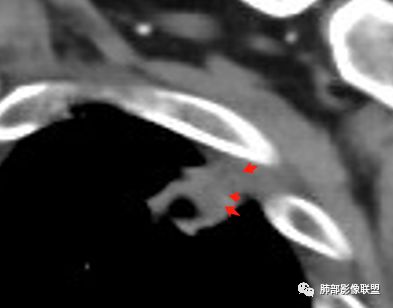

4.可疑胸膜侵犯(栽赃)。

3.内壁凹凸不平。换个视角说,有壁结节,外缘呈分叶状。

4.支气管常截止病灶处,且不会行走厚壁间。

6.胸膜受侵,胸膜外脂肪密度增高;外缘膨隆为主。